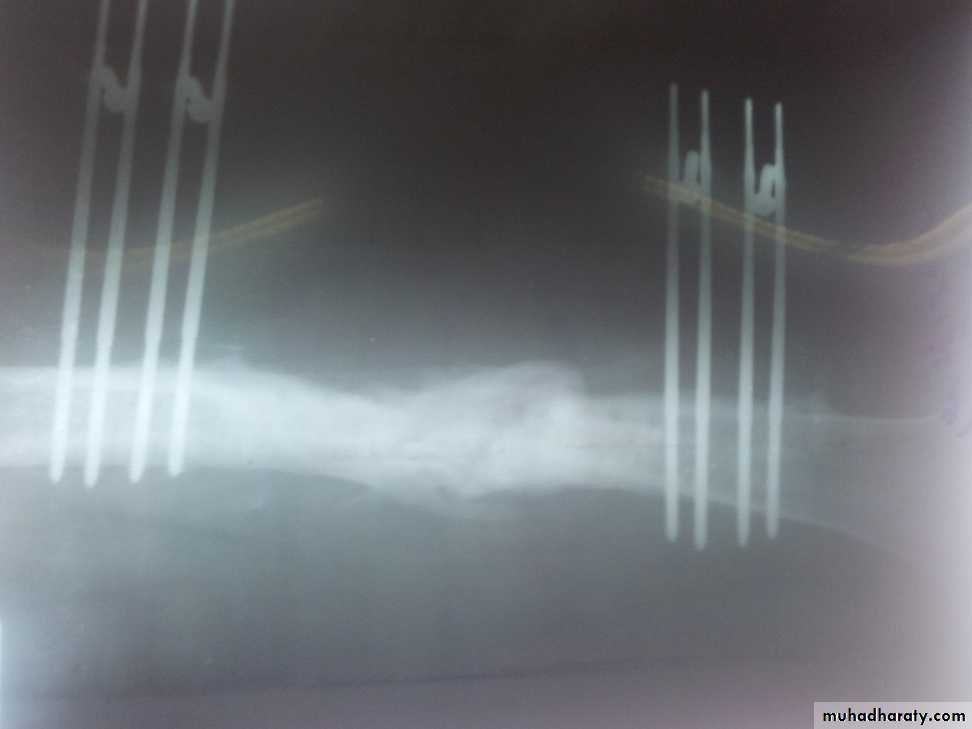

• Treatment: The wound should be left open for inspection and frequent dressing, and then delayed primary closure after few days. The fracture is fixed by external fixator.

Chronic Osteomyelitis

It is used to be a sequel of acute haemtogenous infection, but now it is more frequently follows open fracture or postoperative complication.Pathology:

There is destruction of bone that follows acute infection leaving sequestra surrounded by dense sclerotic bone.

Treatment:

Surgical:

When abscess is formed, it should be incised and drained.

Sequestrectomy (removal of sequestrum) when a sequestra is radiological visible after sequestrectomy the dead space should be injected with antibiotic solution and then allowed to fill with granular tissue, sometimes when the cavity is big, it needs bone graft muscle flap.